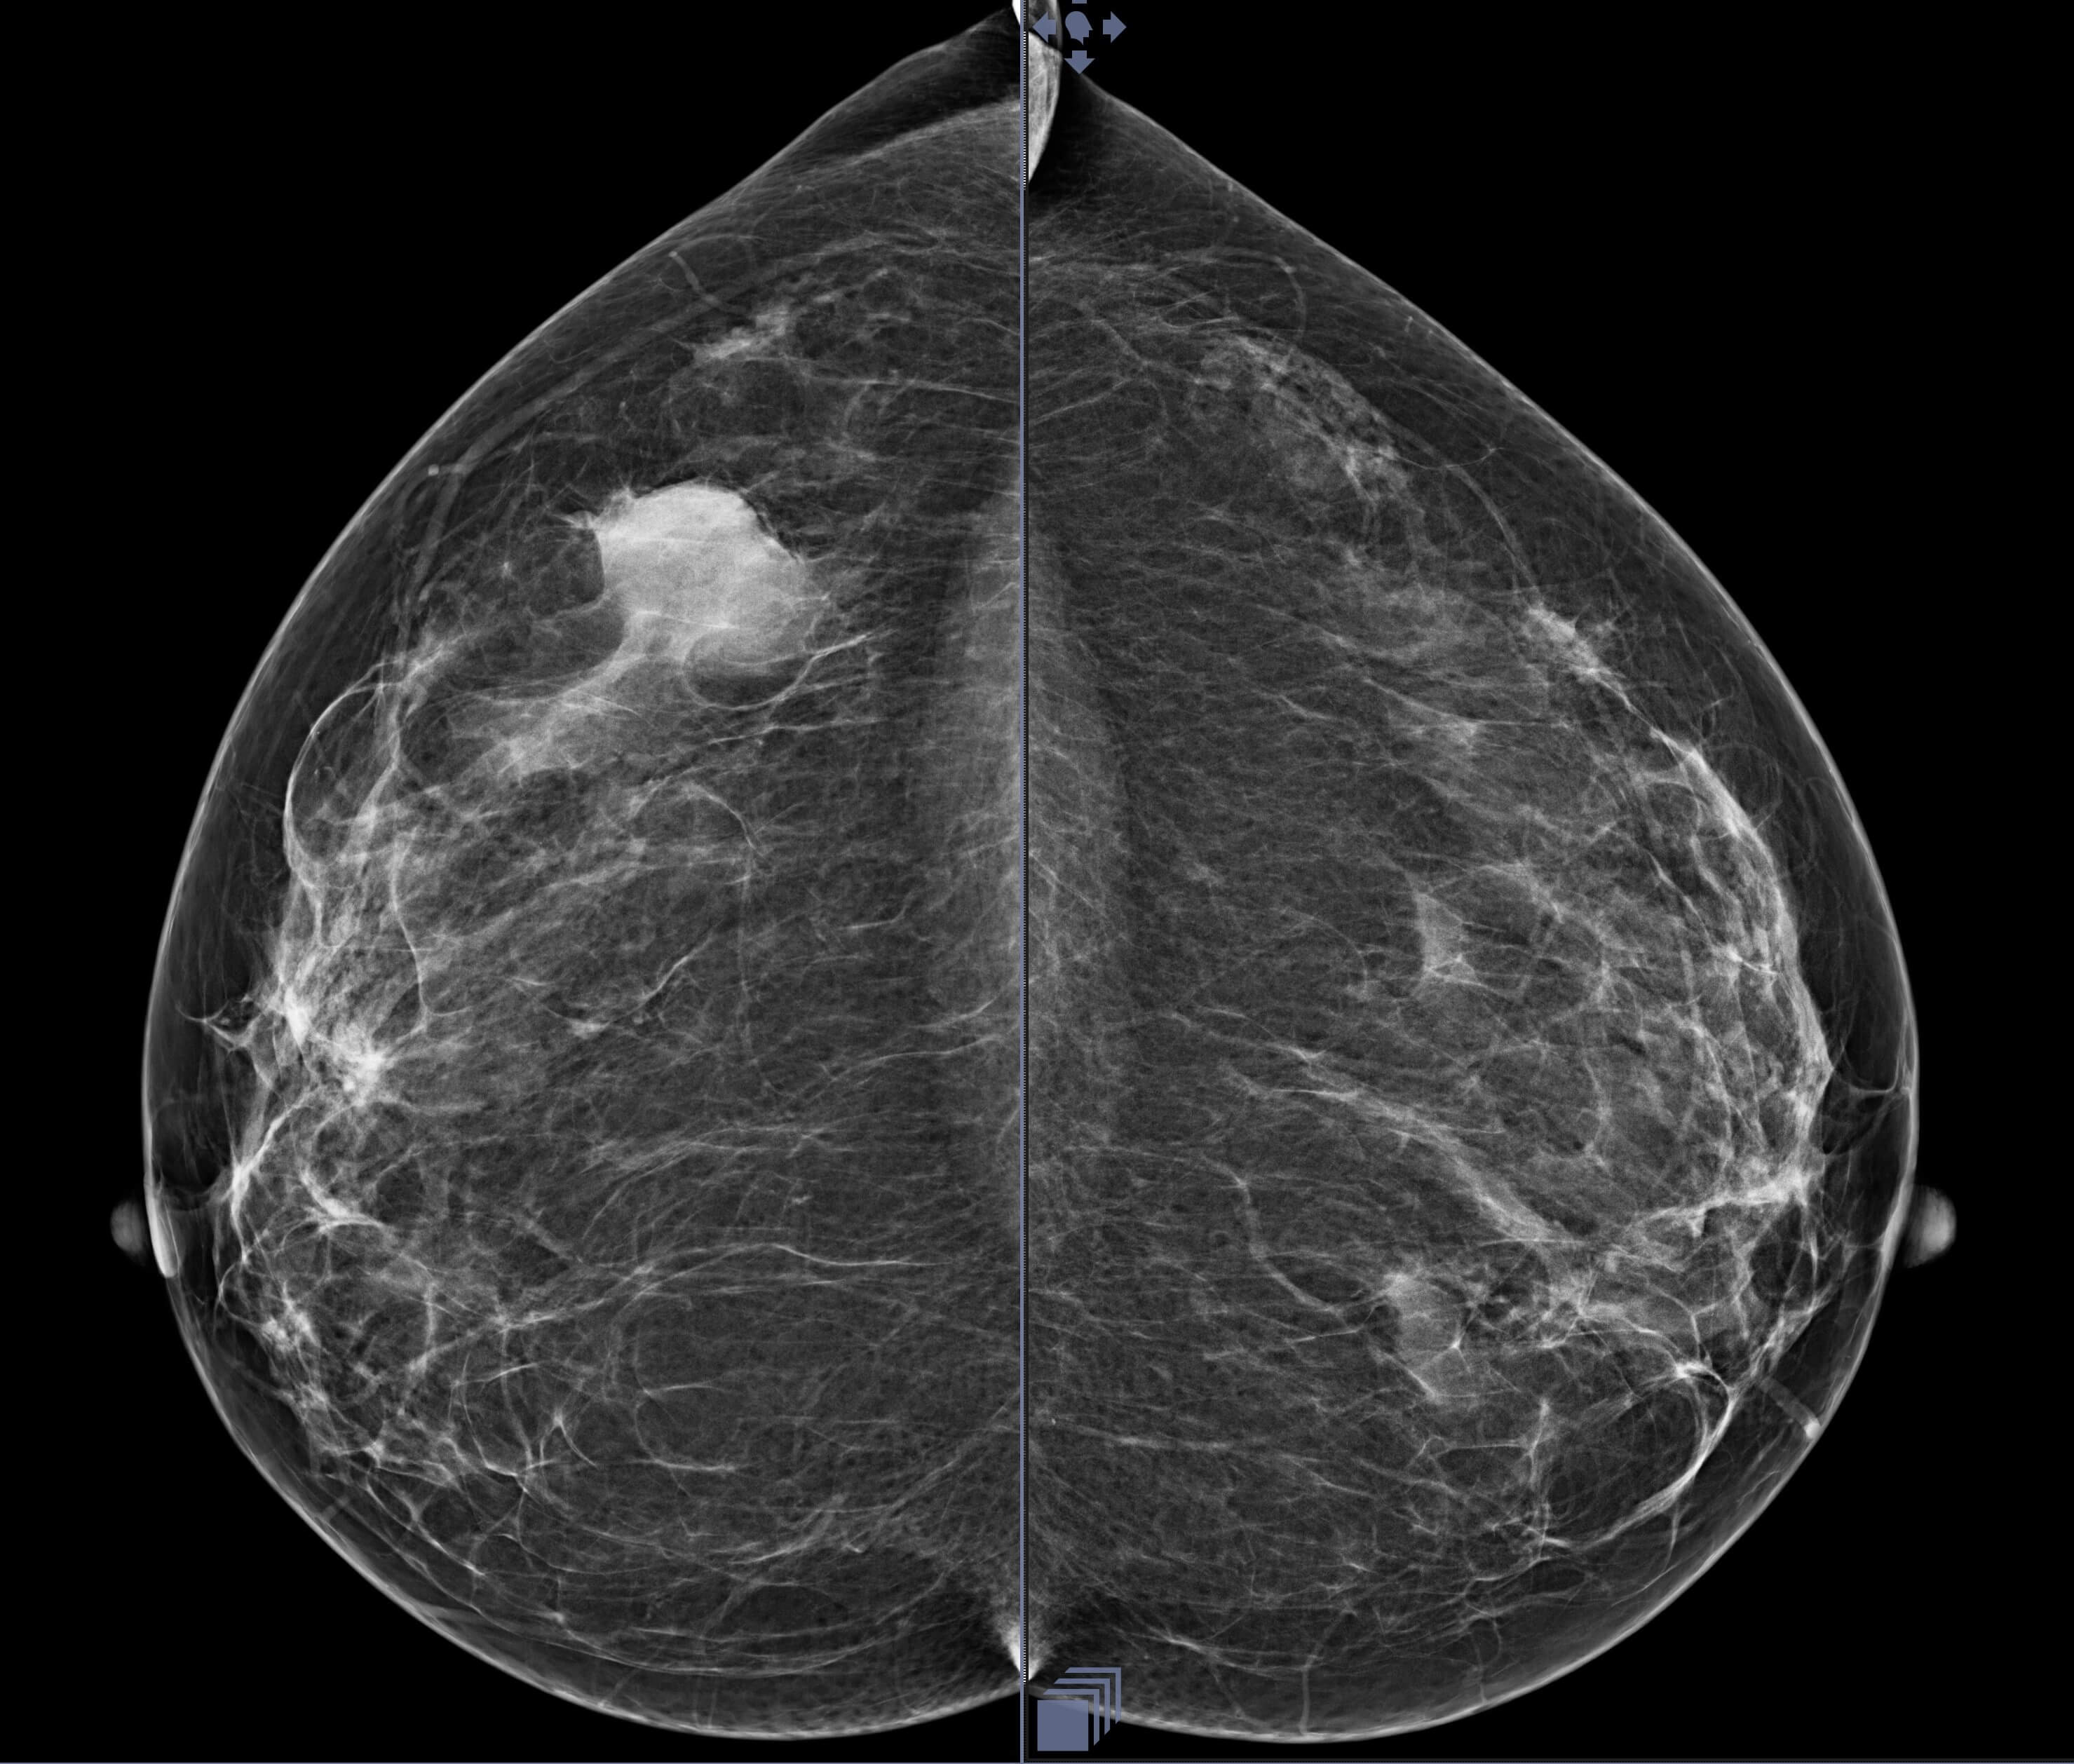

A 48-year-old woman with no family history of breast cancer presented ...

Read More